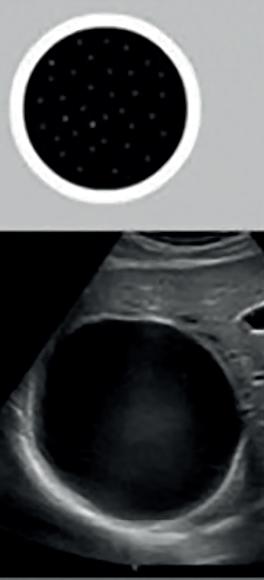

The Positive Effect of Water Immersion on Labor Progress Assessed by Intrapartum Ultrasound Examination

Pozytywny wpływ zastosowania immersji wodnej na postęp porodu oceniany metodą ultrasonografii śródporodowej